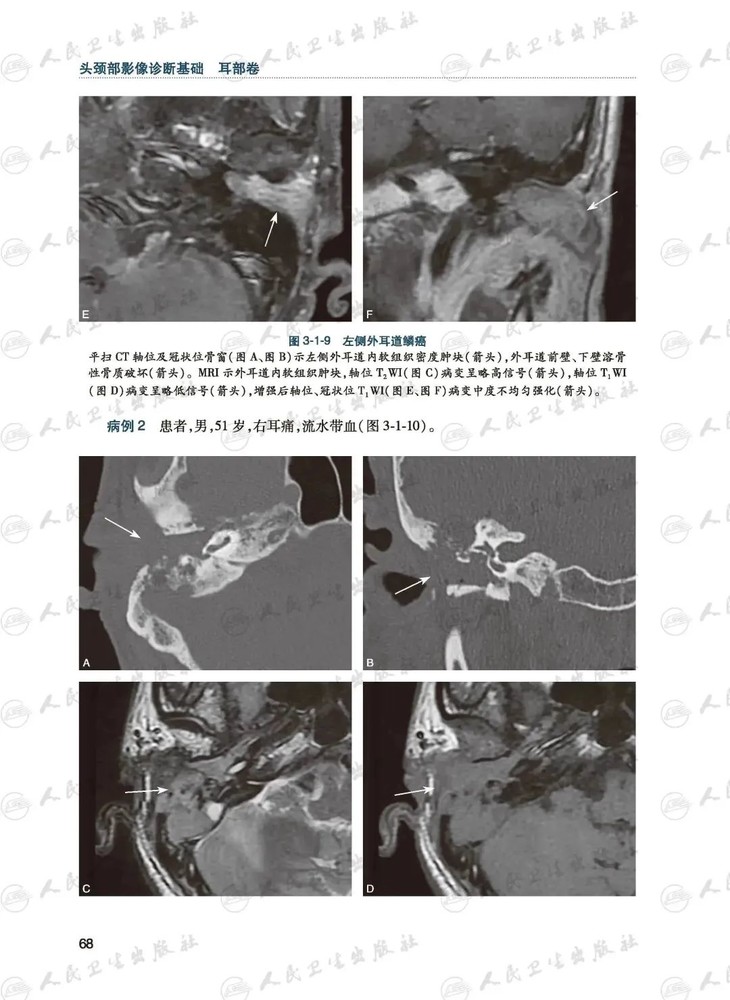

本书共有5章,600余幅图片,围绕耳部影像检查技术以及常见病、多发病的影像征象展开叙述,归纳总结了外耳、中耳、内耳、面听神经、侧颅底颈静脉孔区等部位疾病的影像特点。本书以诊断思路为主线,方便读者快速把握耳部疾病的影像诊断思路;部分章节后附有选择题、名词解释、问答题等练习题,有助于读者检验并巩固所学的知识;“耳部影像报告书写规范”一章,有助于读者结合自身医院的实际情况规范书写影像报告;加入“耳部常见疾病的病理基础”章节,有助于读者分析产生影像征象的病理基础,对疾病进行全方位、多视角阐述,更系统、更全面、更有深度地解决现代耳颅底显微外科的临床实际问题。